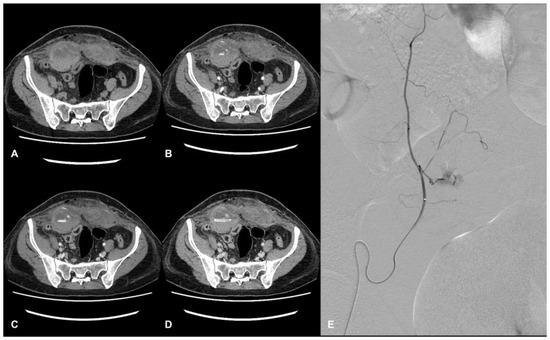

Diagnosing AWHs can be challenging since signs and symptoms are often nonspecific. In this scenario, computed tomography angiography (CTA) is recognized as the gold standard for identifying and characterizing hematomas, allowing for determining the localization of the bleeding site, the extension and the dimensions of the hematoma, and the exclusion of other acute abdominal diseases (Figure 1) [7].

Figure 1.

CT and DSA images of a hospitalized patient with COVID-19. Evidence of a large hematoma within rectus abdominis below the arcuate line in axial CT images. The pre-contrast phase shows the extension and location of the hematoma, showing a fluid level (hematocrit effect) (A). The contrast-enhanced acquisition at the arterial (B), portal (C), and delayed phase (D) show active bleeding within the hematoma. Angiography shows a contrast blush from branches of the right inferior epigastric artery (E).

In COVID-19 patients, Polyaev et al. report that some specific CT signs, such as the presence of a fluid level (hematocrit effect) and the phenomenon of a “signal flare”, in the context of spontaneous hematoma, correlate with active bleeding on DSA, indicating endovascular treatment is needed [11]. The management and the treatment of AWHs can include conservative, endovascular, or surgical approaches; in hemodynamically stable patients with life-threatening AWHs, catheter-directed angiography and embolization have become the primary options for treatment [2].